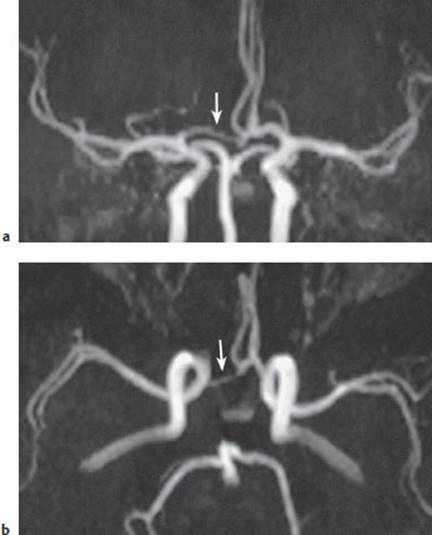

MR angiography. When the spin-echo technique is used in MRI scanning, flowing blood gives rise to a signal only if it is excited by two radio wave pulses arriving one after the other at the same location. If the blood rapidly passes through the imaging plane, the bit of blood that received the first excitatory pulse has already flowed away by the time the second pulse arrives and no signal is generated—the vessel appears dark (there is a “flow void”). However, if the blood flows slowly enough to receive both pulses in the imaging plane, the vessel appears bright. When gradient-echo sequences are used, flowing blood always appears bright, while stationary tissue appears dark. Computer algorithms can combine the individual sectional images, processing them to generate a projectional image resembling a conventional angiogram; this is a magnetic resonance angiogram (Fig. 4.7). With MR angiography, an occluded carotid artery, for example, can be diagnosed noninvasively. Contrast-enhanced MR angiography is currently being performed increasingly often. In this technique, the signal is produced not by the flowing of the blood per se, but by the contrast medium in the bloodstream.

Fig.4.7 MR angiography of the intracranial vessels. a Coronal and b axial projections. The arteries in this study are normal except for hypoplasia of the main stem of the right anterior cerebral a. (arrow).